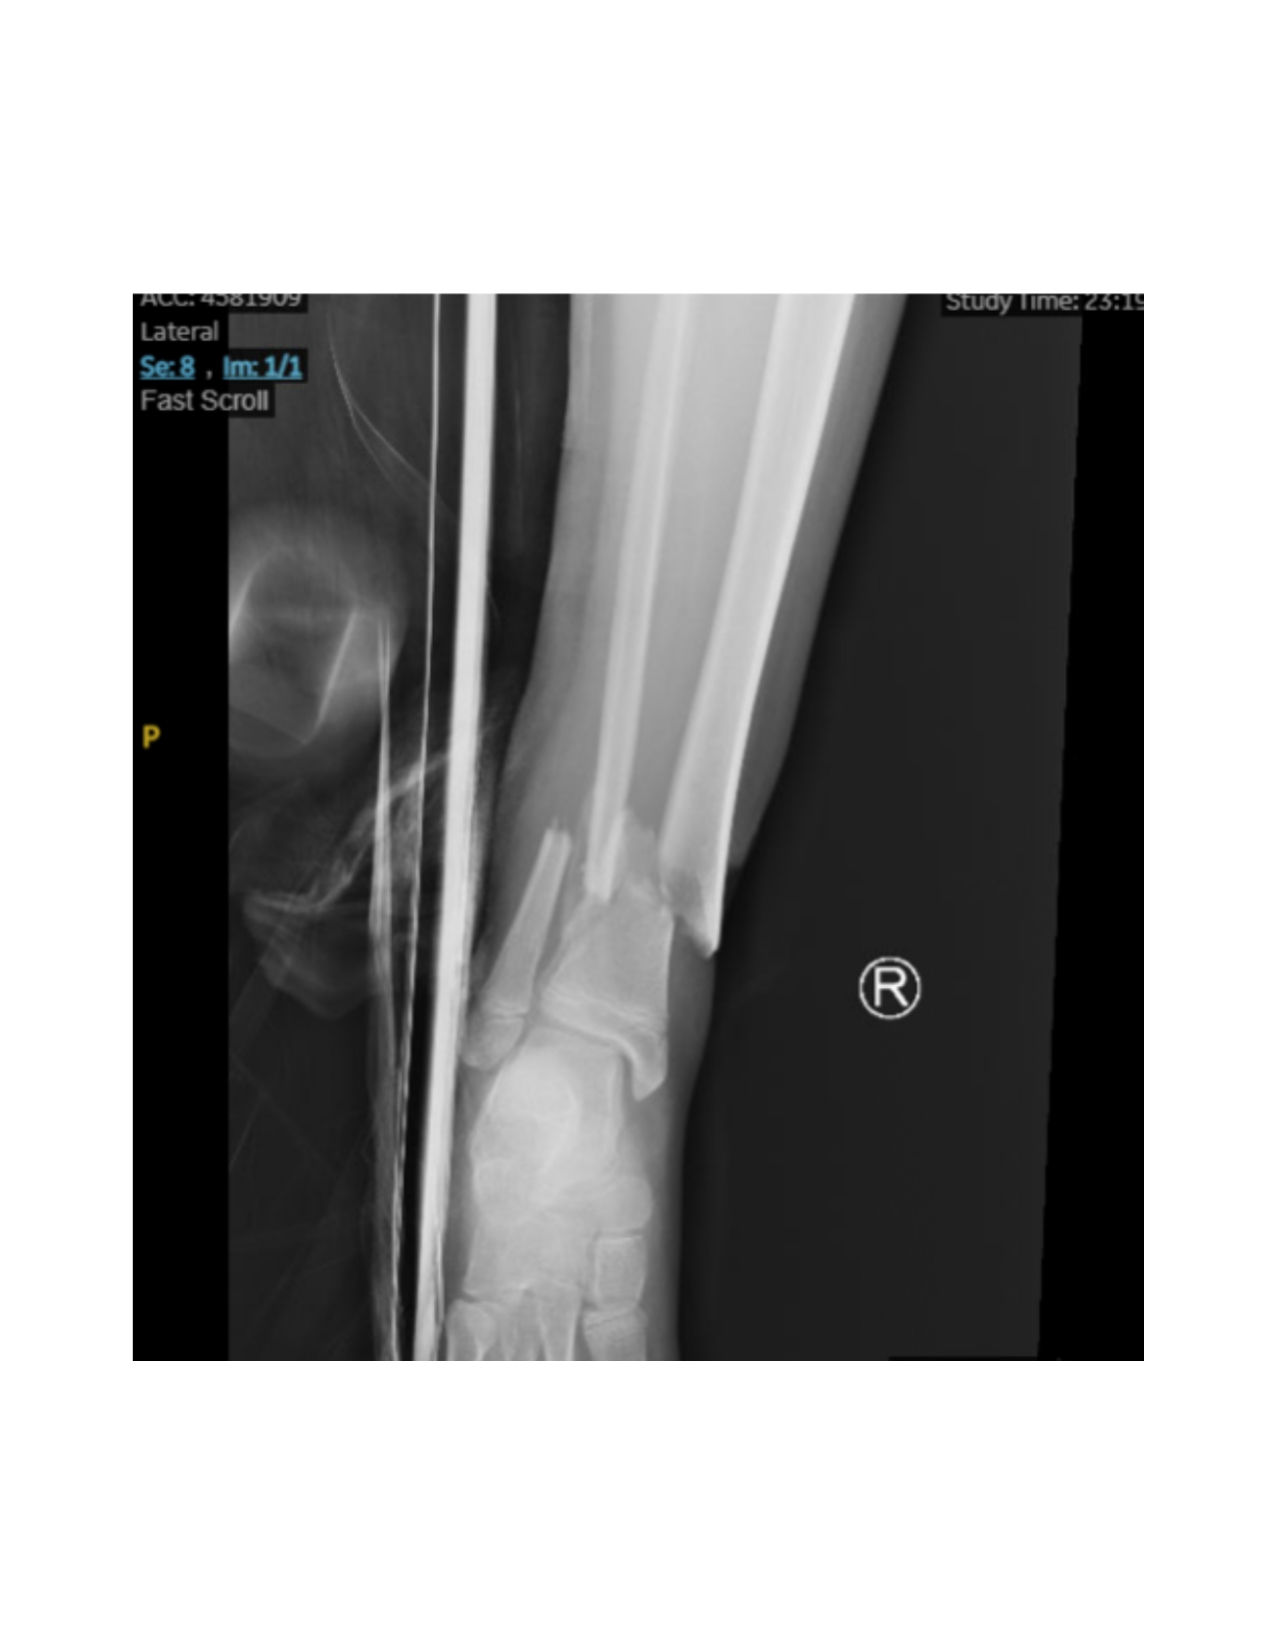

To complete the procedure, the proximal ends of the nails are trimmed and bent into the cortex for future removal. The lateral side of the tibia has a minimized risk of postoperative skin lesions due to protective padding from overlying muscle mass allowing for a sharp bend, while the medial side bend should be less pronounced as the nail lies just beneath the skin (Figure 7).

The fracture site is then reassessed under fluoroscopy to confirm maintained reduction. (Figure 8 and Figure 9) Wounds are irrigated and closed in two layers, followed by sterile dressing and short leg splint application.